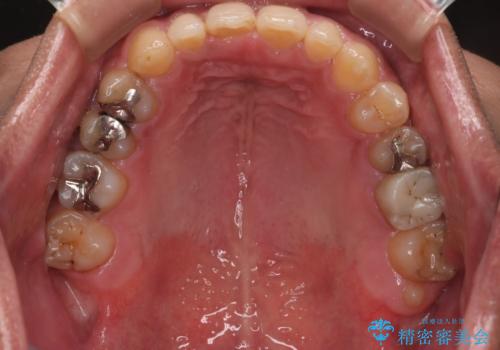

【モニター】インビザライン 前歯の捻れを治したい

- 30代男性

- 矯正装置

- インビザライン

- 治療計画

- 上下の前歯のがたつきを主訴に来院されました。インビザラインで治療可能と判断致しましたので、IPR(歯と歯の間を削る処置)と歯列弓拡大をして

がたつきをとる治療計画を立てました。

マウスピースをしっかり使用していただいたことで、主訴である前歯のがたつきも改善され

リファイメントも1回のみで治療を終了することが出来ました。